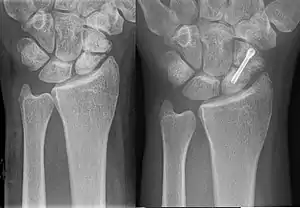

In a hypertrophic nonunion, the fracture site contains adequate blood supply but the fracture ends fail to heal together.[6] X-rays show abundant callus formation. This type of nonunion is thought to occur when the body has adequate biology, such as stem cells and blood supply, but inadequate stability, meaning the bone ends are moving too much. Typically, the treatment consists of increasing stability of the fracture site with surgical implants.[7]